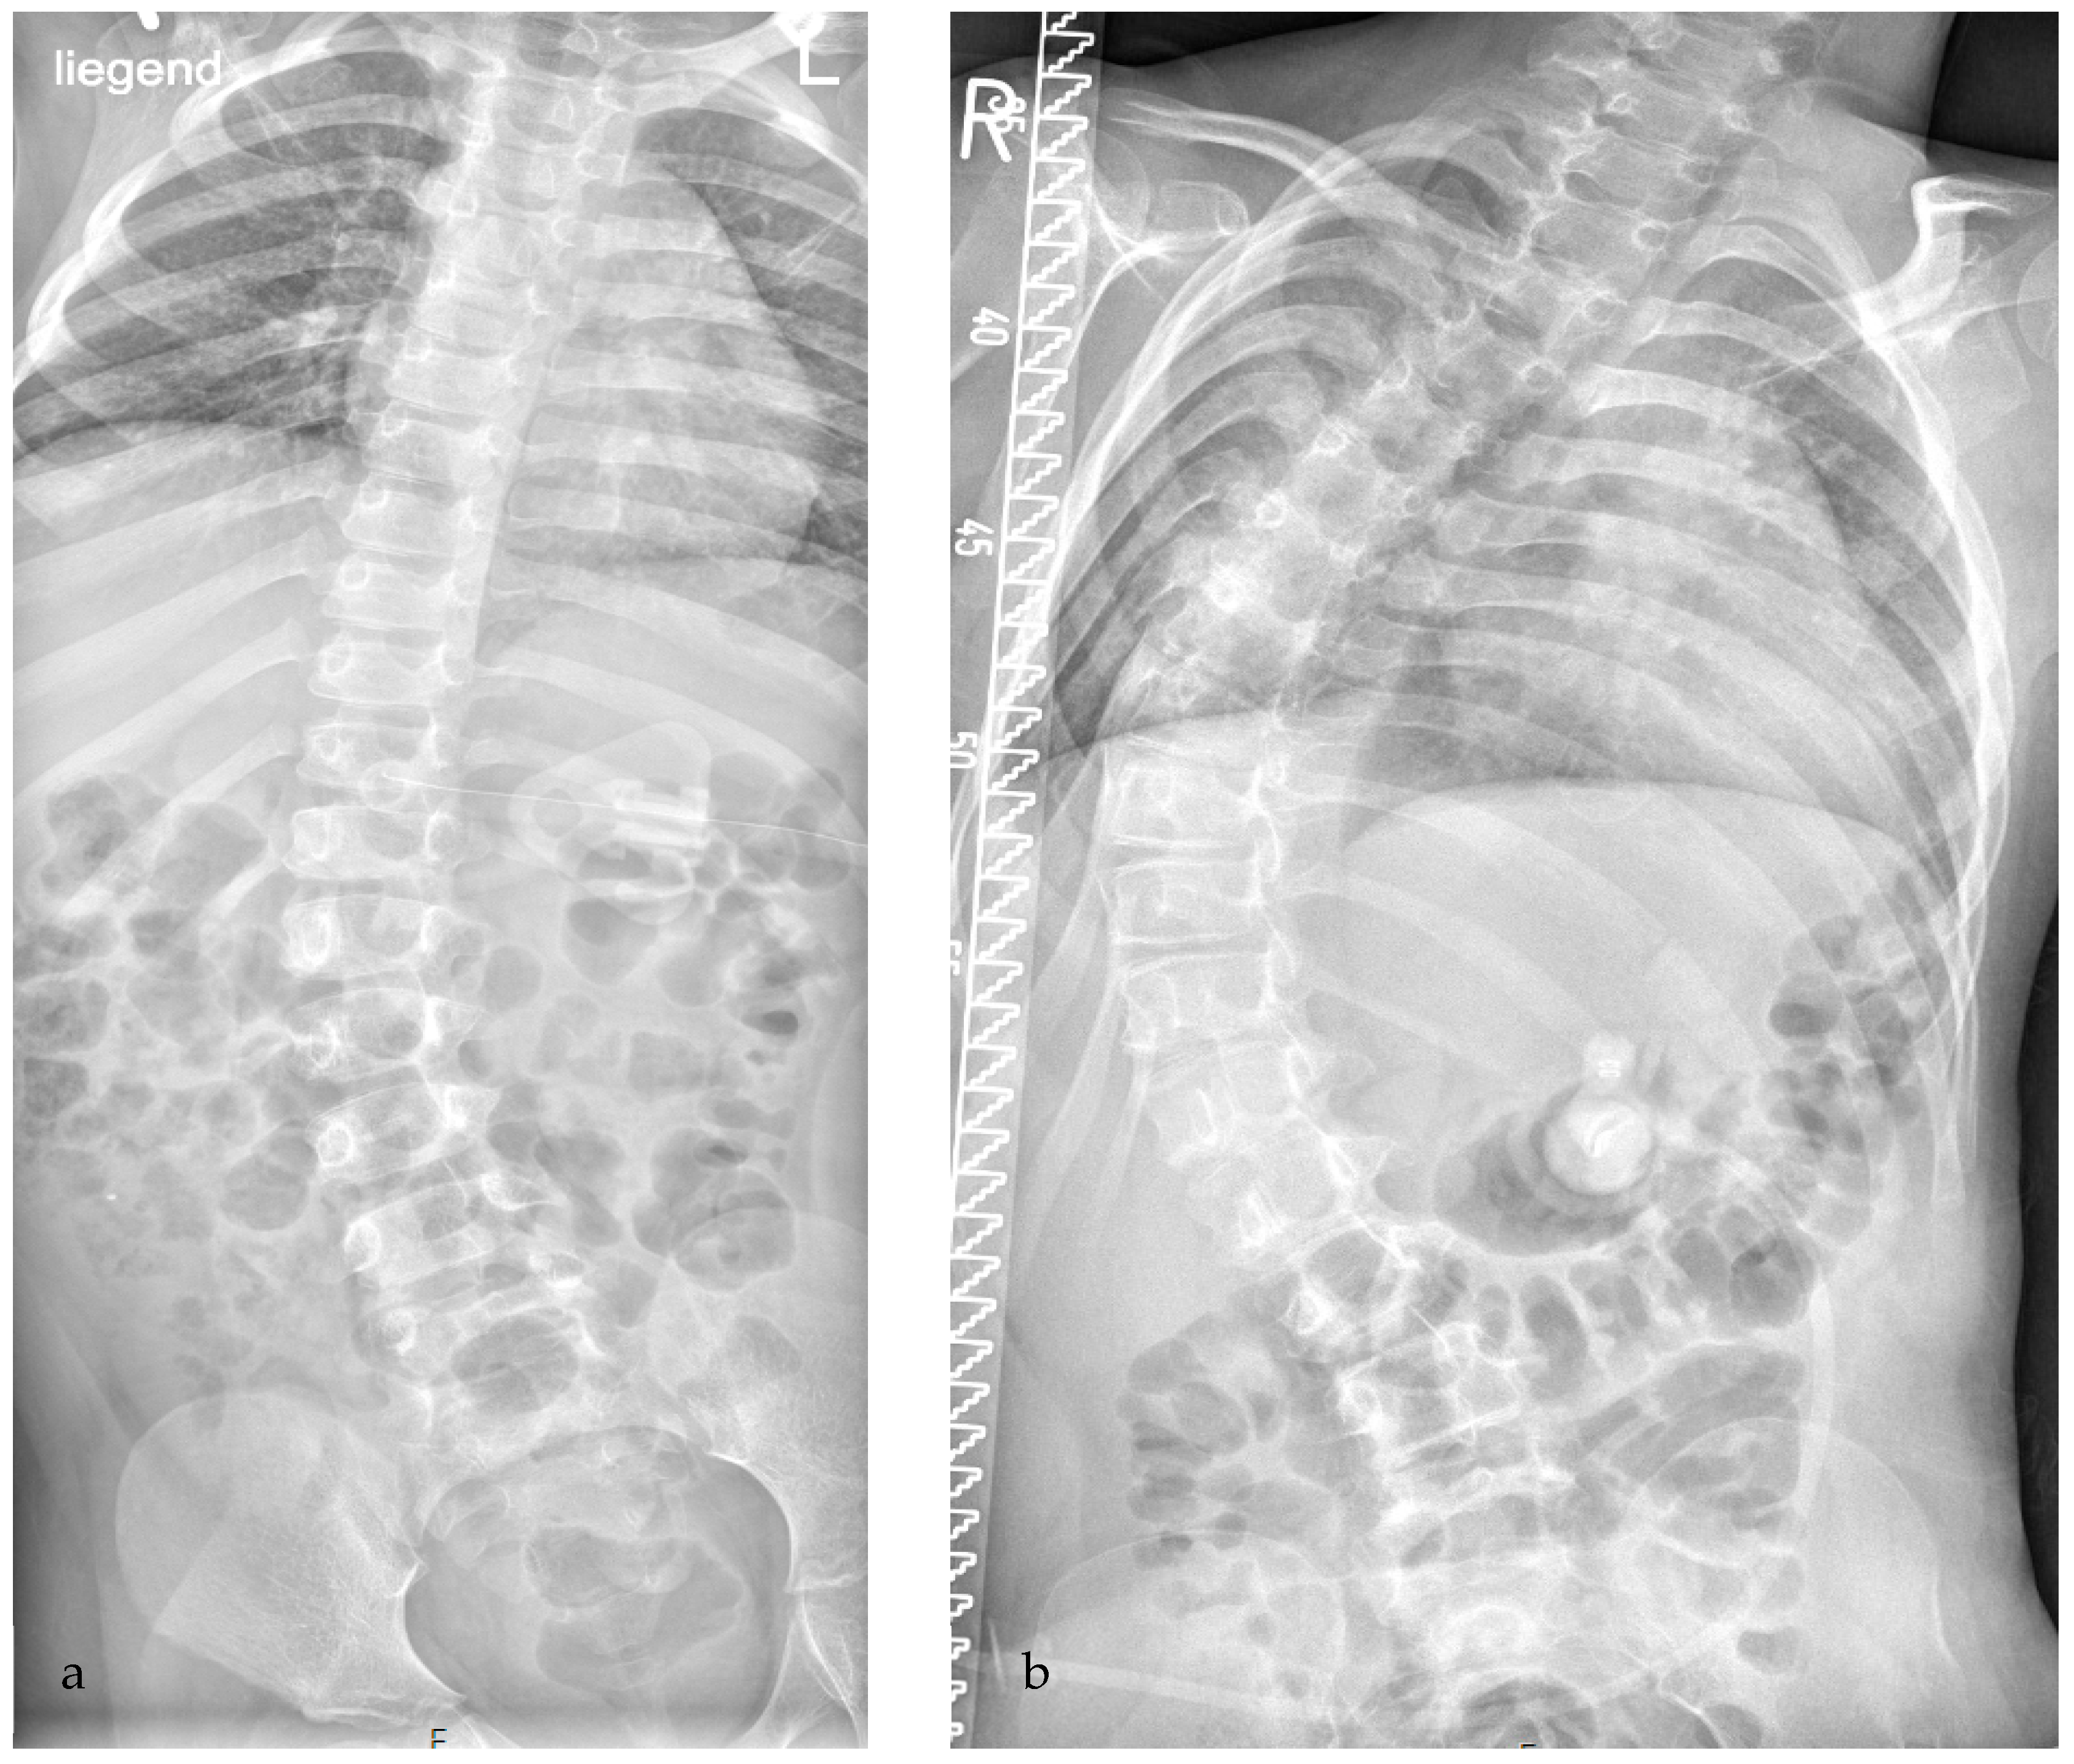

Figure 2. Development of severe scoliosis in a girl with CP, GMFCS level V. (a) At the age of 6 yrs, moderate scoliosis of 27° according to Cobb was detected; no referral to an orthopedic physician was initiated for treatment. (b) At the age of 10 yrs, she was first seen by an orthopedic surgeon with severe progressive scoliosis of 73°; at that point, conservative treatment is very debatable and a surgical intervention will be necessary to preserve quality of life.

However, there are not only hip problems which might develop during growth and should be addressed, there are also spinal problems which might occur in CP children. Unfortunately, at present there is only a limited focus by clinicians and physiotherapists, despite the high frequency of these conditions and the severity of impact on patients’ quality of life. The overall incidence of scoliosis is reported as between 20% and 41% in several studies [7,8,9,10]. Rates of scoliosis further increase with age and GMFCS level: at the age of 10 years, moderate or severe scoliosis has been observed in approximately 1% of the children at GMFCS level I. This rate increases to 2.5% at GMFCS III, 10% at GMFCS IV and 30% at GMFCS V; at the age of 20 years, the corresponding percentages are 5%, 30%, 45% and 80%, respectively [8]. The cause is not entirely clear, but thought to be a combination of spasticity, muscle weakness, impaired muscle control as well as asymmetric muscle tone [8,11]. The deformity is typically progressive, especially during the pubertal growth spurt but also after growth arrest [12]. Severe scoliosis may cause additional motor dysfunction, sitting and transfer problems, compromise pulmonary function and induce pain with reduced quality of life. Finally, associated respiratory insufficiency may be life-threatening. Therefore, early diagnosis and treatment is of fundamental importance to prevent severe scoliosis and to maintain quality of life, especially in the at risk groups GMFCS level IV and V (Figure 2) [8,13,14].